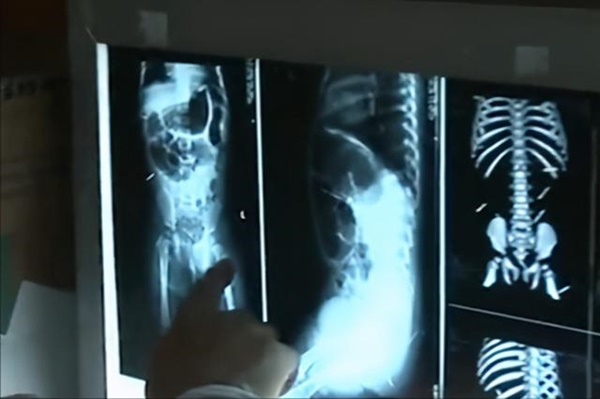

Theo đó, những chiếc kim rải rác ở các vùng mông, khoang bụng, xương chậu và nhiều bộ phận quan trọng khác.

Tử Huyên được đưa đến bệnh viện nhi đồng Bắc Kinh để các chuyên gia phối hợp tìm cách lấy kim ra khỏi người bé.

Các chuyên gia đã nhận định tình hình của Tử Huyên vô cùng nguy cấp vì những cây kim đâm vào các bộ phận quan trọng trên cơ thể, chỉ cần một sai lầm nhỏ trong quá trình phẫu thuật cũng có khả năng khiến bé mất mạng.

Trong quá trình phẫu thuật, đội ngũ y bác sĩ gặp nhiều khó khăn khi vị trí của các cây kim không cố định mà chúng bắt đầu di chuyển trong cơ thể bé nhỏ của Tử Huyên.

Sau 3 tiếng rưỡi phẫu thuật với sự hợp tác của 9 khoa, bác sĩ cuối cùng cũng lấy toàn bộ 12 cây kim ra ngoài, bao gồm 4 kim may vá, còn lại là kim y tế và thậm chí có nhiều cây kim đã bị rỉ sét.